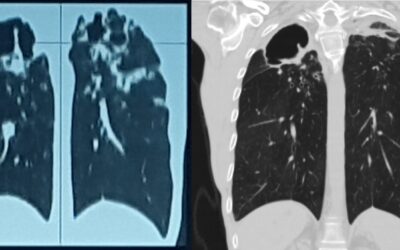

პაციენტი 42 წ მამაკაცი. აქტიური მწეველი. თავს ავად გრძნობს რამოდენიმე თვეა. ჩივილები: ძლიერი ქოშინი ფიზიკურ დატვირთვაზე, ჰაერის უკმარისობა, საერთო სისუსტე. გულმკერდის კტ კვლევით - ორივე ფილტვის ზედა წილებში გაიშვიათებული ფილტვის ქსოვილი, გიგანტური ბულები 10-14 სმ...